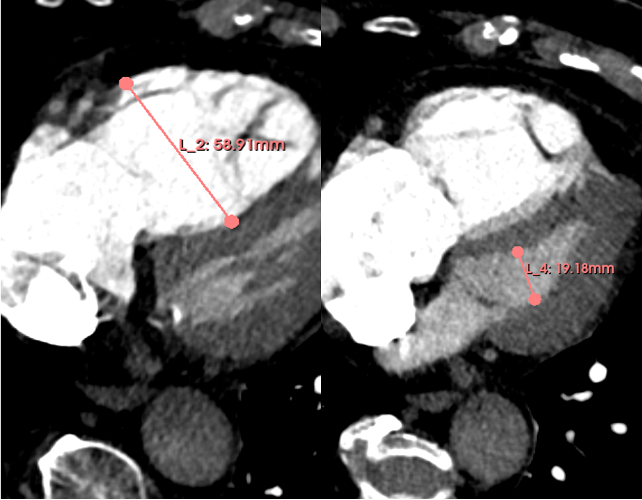

Methods: We conducted a retrospective analysis of 102 CT scans (Siemens-Sensation 128) of patients diagnosed with acute intermediate-high risk PE between 2019 and 2025, as recorded in the Chemnitz PE Registry (CLoT). RV/LV ratio was measured in the axial plane at the largest diameters of the right and left ventricles (Figue 1). TV and TSA were quantified using the software platform for medical image processing “3D Slicer” (Version 5.8.1;Figure 2). For statistical analysis patients were divided in 4 groups by quartiles (Q) based on their mean RV/LV-Ratio. Spearman rank correlation and Kruskal-Wallis-Tests were used to evaluate associations between RV/LV ratio and TV or TSA. Statistics was done with R using Rstudios.